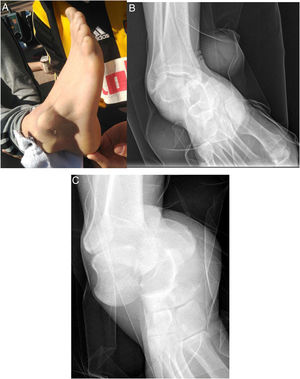

Swelling, haematoma, and deformity were a consistent feature of the physical examination of the patients (100%), with all open dislocations being associated with injury (4). According to the Gustilo and Anderson classification, we had two type IIIA and two type IIIC open dislocations, requiring the involvement of the plastic and/or vascular surgery teams. The two-type IIIC open dislocations correspond to the two cases listed in Table 1 with neurovascular injury (section of the anterior tibial bundle and section of the posterior tibial bundle). In terms of the subtype of periastragaline dislocations according to the direction of clinically and radiologically observed dislocation (Fig. 1), there was a predominance of medial dislocations (9) over lateral dislocations (4).

32-Year-old man with pain and deformity in the right foot after forced inversion. The protrusion of the lateral aspect of the talus into the skin can be seen (A). The anteroposterior radiograph shows loss of subtalar congruence, with the calcaneus in a medial position to the talus (B). Lateral radiograph shows loss of congruity at Chopart's joint (C).